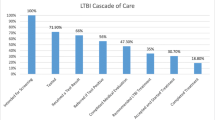

There are several regimens available for the treatment of LTBI among people living with HIV (Table 1). Currently in the US, guidelines recommend testing for latent TB infection using TST or IGRA at the time of HIV diagnosis, regardless of epidemiological risk factors for TB exposure. PLWH, CD4+ counts <200 cells/μL, and negative tests for LTBI should be retested once they have started antiretroviral therapy (ART) and CD4+ counts are over 200 cells/μL. Annual testing (using TST) is only recommended for PLWH if they are at high risk for repeated/ongoing exposure to people with active TB [31]. In the US, treatment for LTBI is only recommended for PLWH who test positive for LTBI [28,29,30]. According to the WHO guidelines, PLWH who have an unknown or positive TST (and are unlikely to have active TB) are recommended to receive treatment for latent TB infection. HIV-negative persons are recommended to receive treatment if they are household contacts of a person with pulmonary TB or if they belong to other at-risk groups [26, 27].